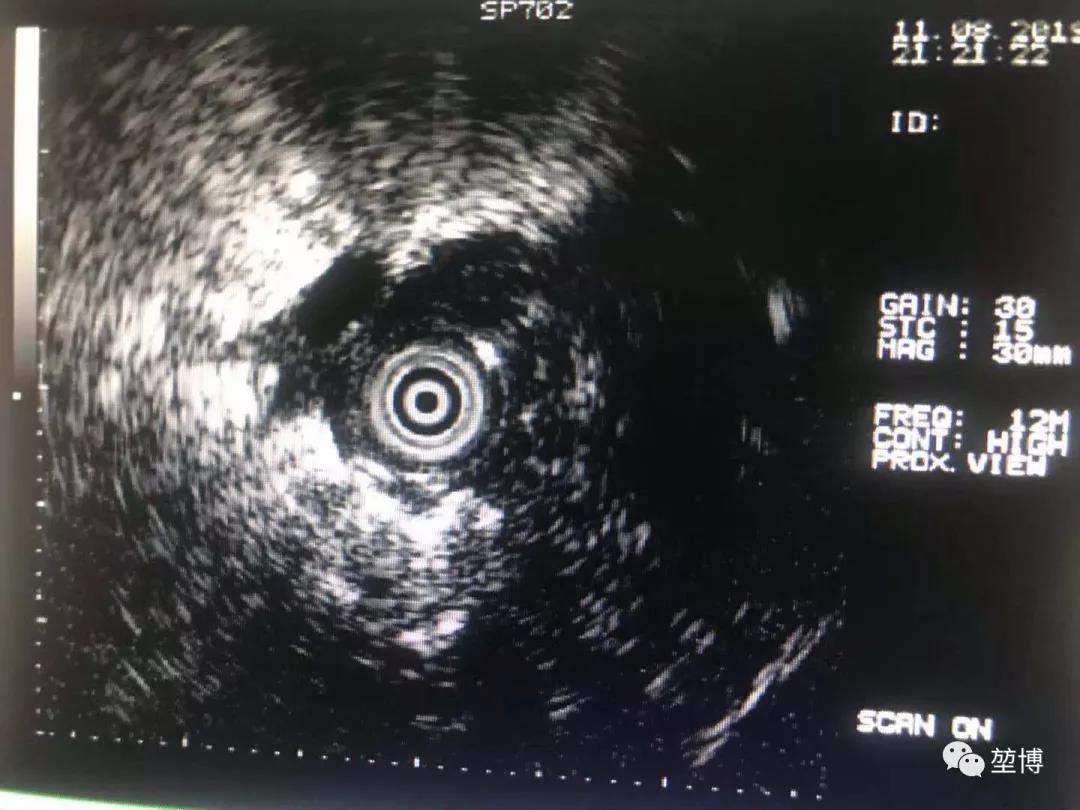

在LungPro引导下抵达RB3开口处,按照术前规划的避开血管的POE穿刺点进行穿刺,X光透视下鞘管顺利抵达病灶中央,经肺实质建立隧道,再将激光光纤送入,行激光消融术。

超声确认抵达病灶

消融后,可见激光纤维前端残留明显碳化组织。